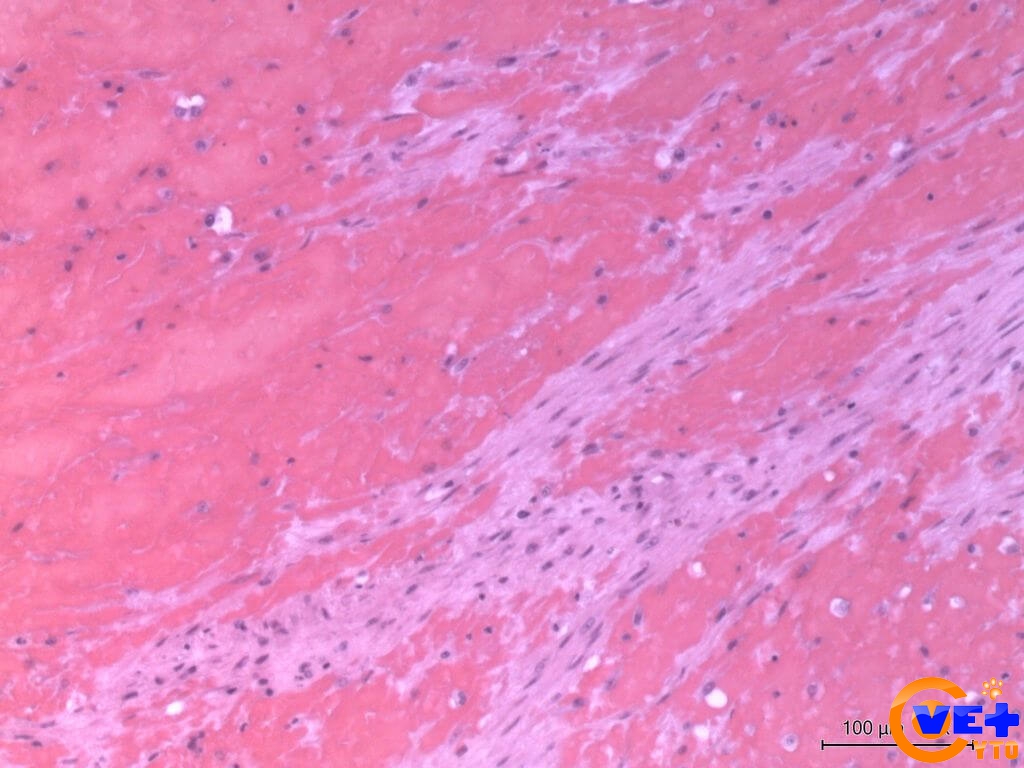

Межуточный миокардит: гистологические исследования